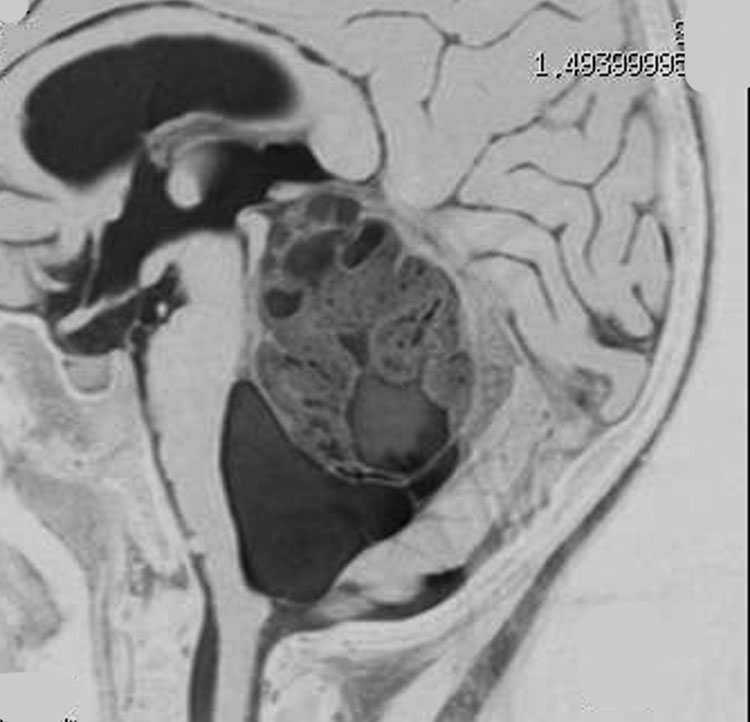

同じような小児例です

右側は手術直後のFLAIR像です。小児ですから大きなのう胞はすぐに潰れて小脳がもどります。白質損傷もなく腫瘍は摘出できています。